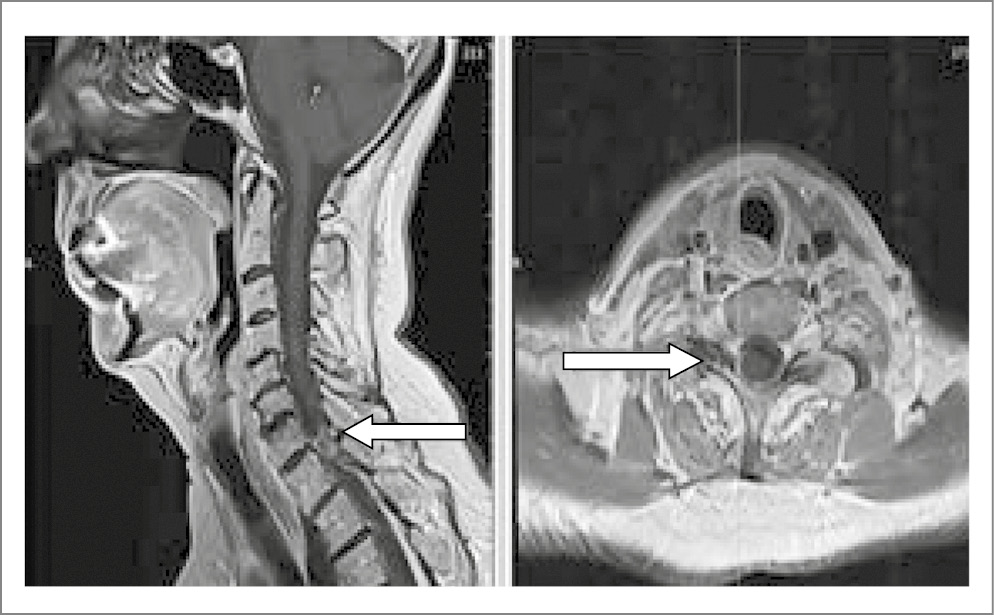

Из анамнеза заболевания известно, что впервые боли в шейном отделе позвоночника отметила в феврале 2024 г. на фоне тяжелой физической нагрузки. Боль изначально локализовалась в шейном отделе позвоночника, спустя 7 дней распространилась в область правой лопатки, а также появилось онемение по всему предплечью справа до IV–V пальцев правой кисти, в связи с чем пациентка обратилась к неврологу. Назначен кратковременный курс нестероидных противовоспалительных препаратов (НПВП), миорелаксантов с временным положительным эффектом, однако после отмены препаратов боль вернулась. Назначены пассивные методы физиотерапевтического лечения, такие как массаж, магнитотерапия. В связи с сохранением болевого синдрома (БС) пациентка обратилась к нейрохирургу, проведена блокада фасеточных суставов на шейном уровне С6-C7 с положительным эффектом в виде снижения интенсивности БС до 3 баллов по ВАШ в течение недели. В конце мая 2024 г. вновь отметила нарастание интенсивности БС до 7 баллов по ВАШ, проведены периартикулярные блокады фасеточных суставов C3/C7. Симптоматика регрессировала в течение месяца, сохранялось эпизодическое онемение в правой руке. С июля 2024 г. боль и онемение вернулись и стали постоянными. По данным магнитно-резонансной томографии (МРТ) шейного отдела позвоночника выявлены ПАК на уровне С7-Th1 справа, стеноз позвоночного канала на уровне С7-Th1 (рис. 1).

Рис. 1. МРТ шейного отдела позвоночника пациентки О.

ПАК на уровне С7-Th1 справа (показана стрелкой), стеноз позвоночного канала на уровне С7-Th1.